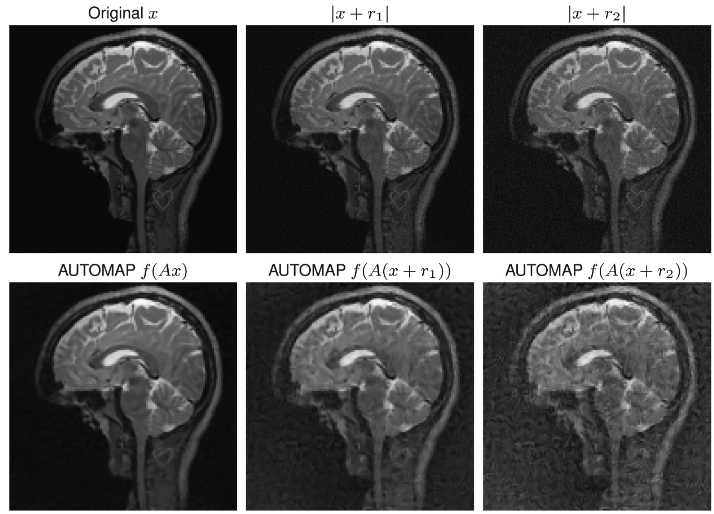

3. Deep models in Inverse Problems

How should standard restoration approaches be adapted to exploit deep learning models?